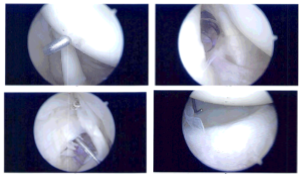

There was a partial articular sided rotator cuff tear. The decision was made to repair the rotator cuff. Debridement of the rotator cuff edges was done. Bony attachment was decorticated and prepped using a burr. The path for the SwiveLock was checked using a spinal needle followed by an incision.

The SwiveLock was inserted after punch insertion. Once the anchor was in place, one limb of the satire was retrieved using a bird beak through the medial rotator cuff the scope was entered into the subacromial space.

The sutures were visualized. The suture was knotted. A good repair was achieved. There was no subacromial bursitis or fraying. The AC joint looked good. Final pictures were taken and saved.

Intraoperative Arthroscopic Images